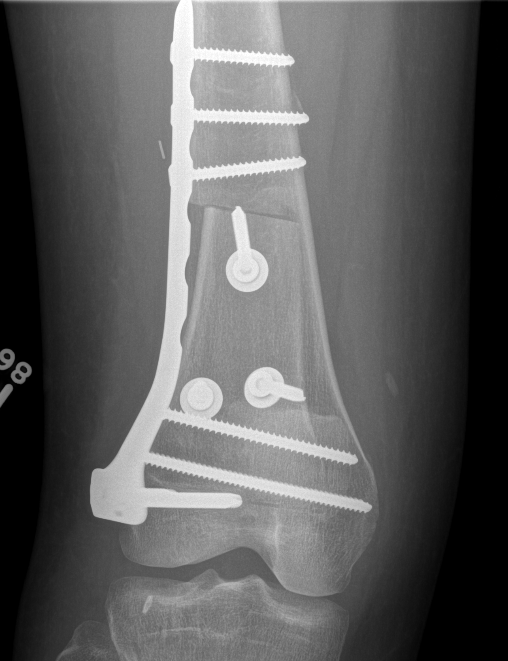

Parosteal Osteosarcoma proximal tibia

A. Hemicortical resection and posterior hemicortical allograft reconstruction